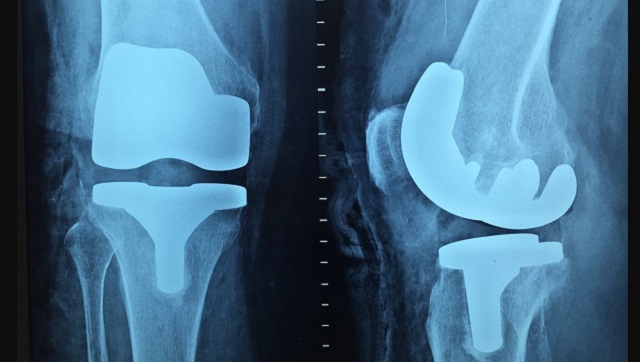

Using hospital records or death certificates apart from diet data, the researchers estimated the risk of total and site-specific fractures among these participant groups. In site-specific fractures, they evaluated the risk of arm, wrist, hip, leg, ankle, clavicle, rib and vertebrae fractures. Over an average of 17.6 years, the researchers observed a total of 3,941 cases of fractures, 566 arm fractures, 899 wrist fractures, 945 hip fractures, 366 leg fractures, 520 ankle fractures and 467 other main site fractures. Risks of total and site-specific fractures The researchers observed that vegetarians and vegans had a higher risk of total fractures than non-vegetarians. Given that vegetarians and vegans usually tend to have lower BMI, and many also take dietary supplements of calcium and plant-proteins to make up for deficiencies, the researchers further adjusted their evaluation accordingly. Even then, the risks of total fractures remained significantly high for vegans and vegetarians. When it comes to site-specific fractures, the findings were more varied. After adjusting for socio-economic factors that affect nutrition, lifestyle habits and body mass index (BMI) of the participants, the researchers found that the risks of hip fracture were higher in fish eaters, vegetarians and vegans. Vegans were also found to have higher risks of leg, clavicle, rib and vertebral fractures than meat-eaters. No significant differences in risks between diet groups were observed for sites like arms, wrists or ankles, although a higher risk of arm fractures was observed in both vegetarians and vegans before BMI adjustments were made. The study also confirmed that postmenopausal women (especially those who were vegan) and participants who had low physical activity levels, lower BMI and were above the age of 50 years had an increasing risk of fractures with age. The researchers concluded that those who had a vegan diet were at the highest risk of fractures, no matter what the site. This, they explained, was mostly due to the low BMI that most vegans have, which prevents fat accumulation and therefore reduces cushioning around the main fracture sites, especially the hips. Muscle strength, which is determined by protein intake and exercise levels, is another major factor in fractures and the study suggests that vegans and vegetarians both have lower lean muscle mass and grip strength. This could also lead to the higher risks of fractures in these groups. In conclusion, vegans and vegetarians need to focus on maintaining a healthy BMI and including proper calcium and protein supplements in their diets to prevent fracture risks. For more information, read our article on Fractured bones. Health articles in Firstpost are written by myUpchar.com, India’s first and biggest resource for verified medical information. At myUpchar, researchers and journalists work with doctors to bring you information on all things health.